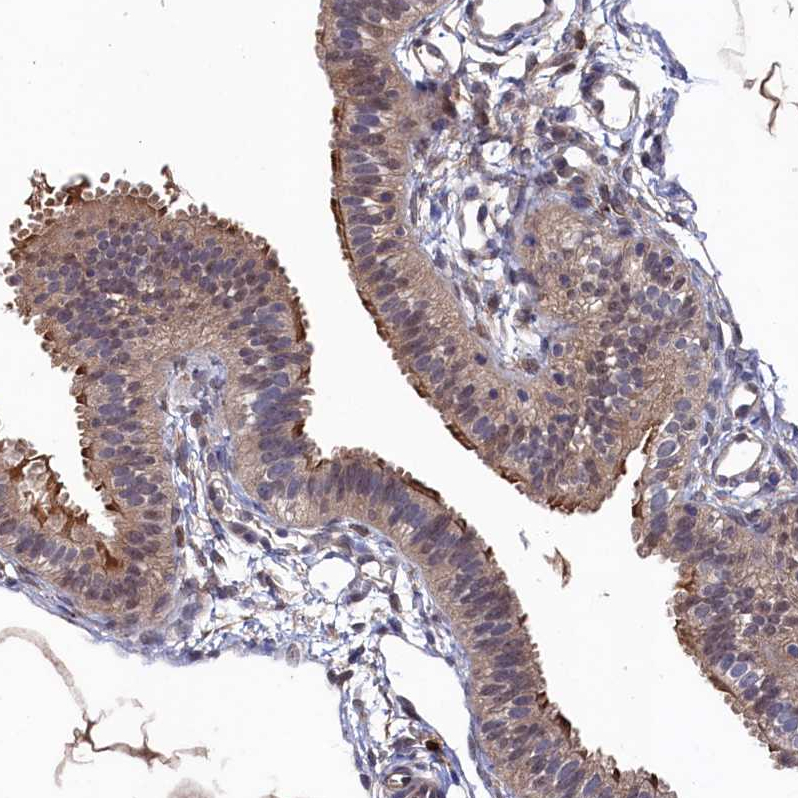

Immunohistochemical staining of human fallopian tube, kidney, prostate and testis using Anti-RNH1 antibody HPA040781 (A) shows similar protein distribution across tissues to independent antibody HPA039223 (B).